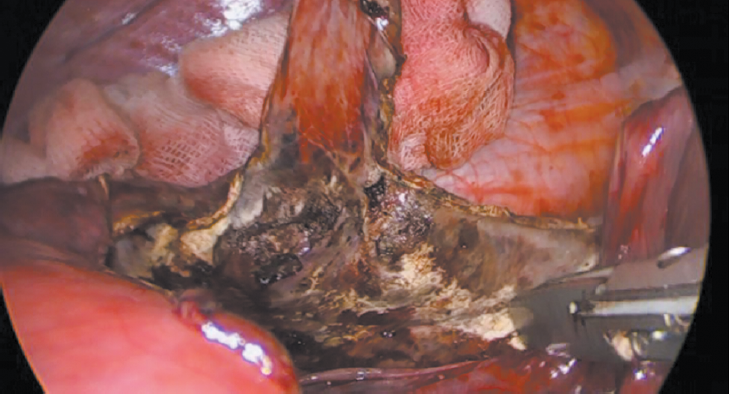

Кроме того, выполнено СКТ органов брюшной полости, при котором установлено, что в VII, VIII сегментах, субкапсулярно, определяется кистозное образование с четкими контурами, неправильной формы, размером 120 × 110 × 101 мм (рис. 1).

Рис. 1. МСКТ-картина кистозного образования печени

Fig. 1. MSCT image of hepatic cyst lesion